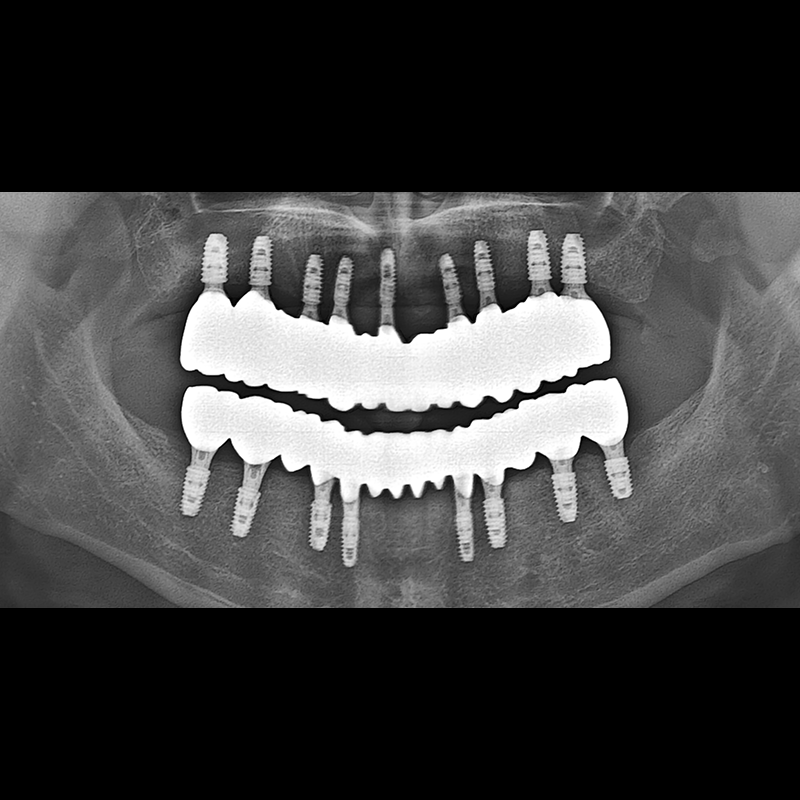

BEFORE AFTER

种植牙前后的照片 2025.05.30

在缺失的牙齿部分和难以挽救的牙齿位置植入了种植牙。